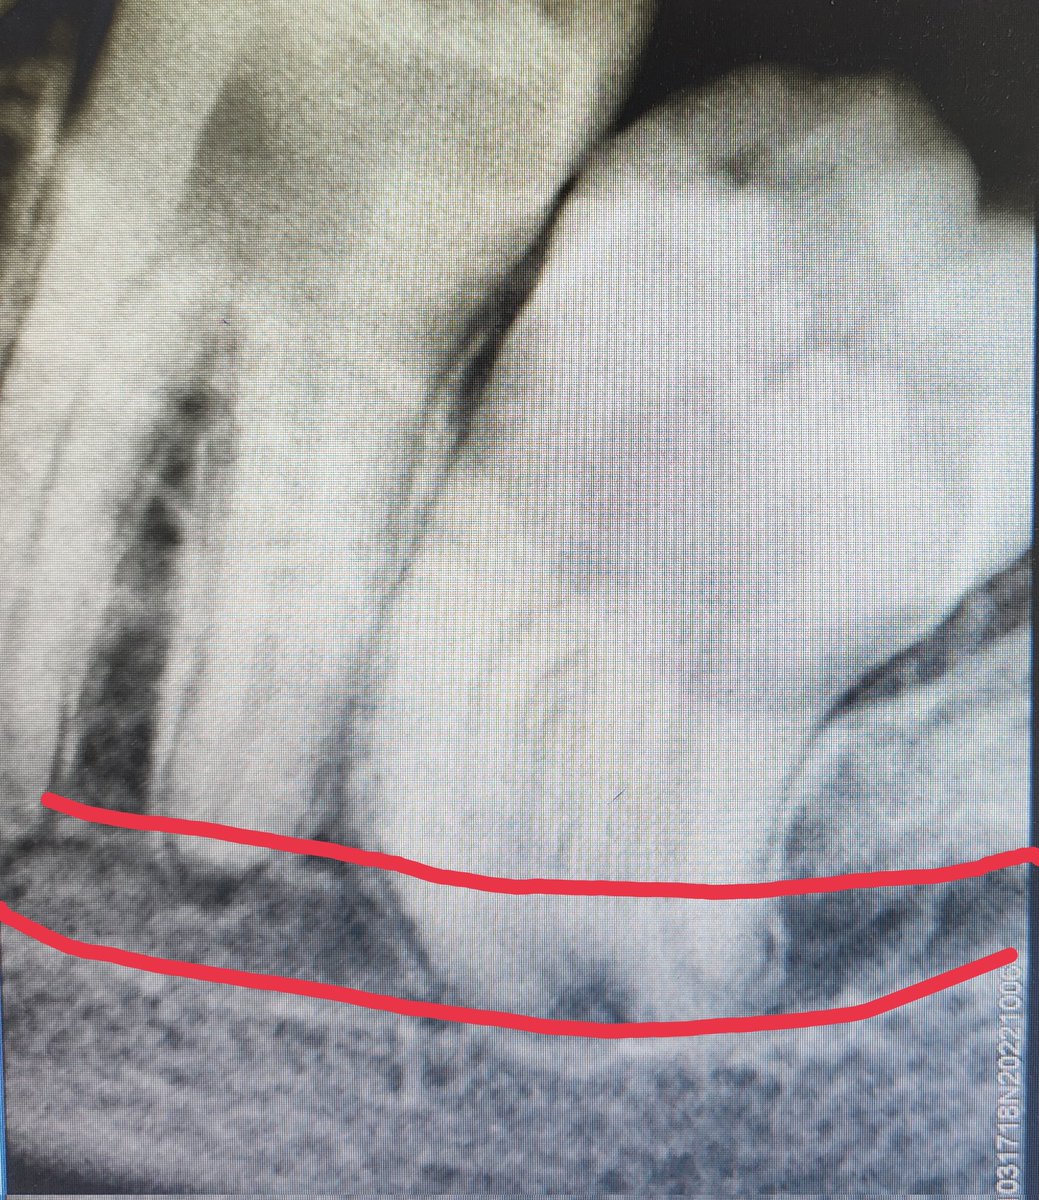

العصب السنخيalveolar nerve يكون احيانا في وضع قريب جدا من ذروة جذور اضراس العقل

هل فعلا ان العصب السنخي يلتصق بذروة جذر ضرس العقل

ام انهما يكونان متجاوران وقريبين من بعض لدرجة عالية قد تتسبب في شعور المريض بالم حاد اثناء الخلع رغم التخدير

الاضراس السفلية تكون في بعض الاحيان قيبة جدا ومتداخل مع قناة العصب السنخي

احد الحلول اذا كان الخلع فيه مخاطرة هو ان نبقي على قمة الجذور داخل العظم تفاديا لجرح العصب

الاشعة المقطعية مفيدة جدا